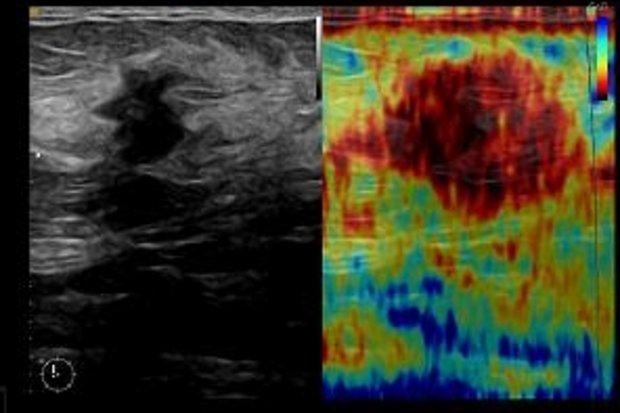

The specialized breast diagnostics under the direction of Dr. In addition to digital x-ray examinations, specialized 3D sonography and elastography, Duda offers gentle, precise, minimally invasive diagnostic diagnostics controlled by imaging processes. Magnetic resonance tomography of the breast is used in accordance with the guidelines for extended diagnostics. In close cooperation with the Institute of Pathology under the direction of Prof. Moll. the result of tissue sampling is available the next day. In this way, the time of uncertainty for women in the event of a conspicuous examination finding can be reduced to a minimum.